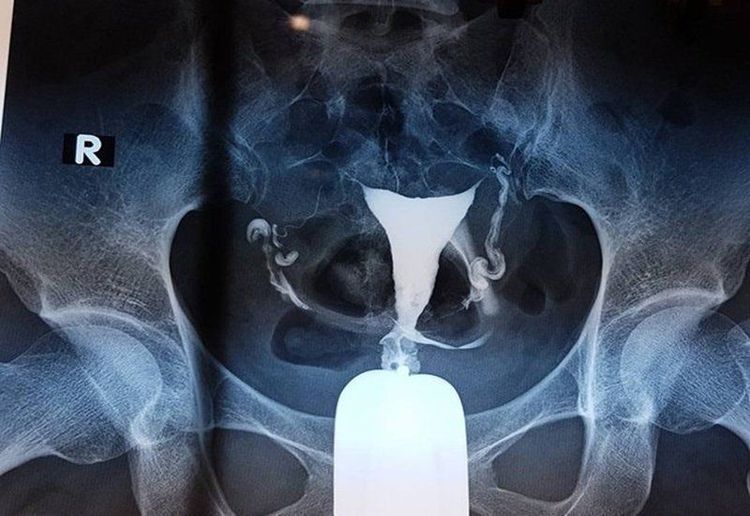

Theo đó, phương pháp này khảo sát bàng quang bằng cách chụp X quang, sử dụng thuốc đối quang iod tan trong nước nhưng thuốc được sử dụng sau khi chọc kim trực tiếp vào bàng quang qua da, trên vùng xương mu.

• Phim chụp lúc bàng quang đầy (300-400ml thuốc đối quang và nước muối sinh lý).

• Bàng quang bờ đều, đáy bàng quang bình thường ở sát bờ trên khớp mu

• Khảo sát khẩu kính và bờ niệu đạo, ở niệu đạo nam bao gồm có 4 đoạn: đoạn tiền liệt, đoạn màng, đoạn hành và đoạn hang.

• Ở niệu đạo của nữ giới là ống thẳng hướng từ trên xuống dưới và từ sau ra trước.

• Không có hiện tượng trào ngược bàng quang niệu quản thụ động hoặc chủ động.

• Không sa cổ bàng quang thì đi tiểu.

• Không có nước tiểu tồn lưu.